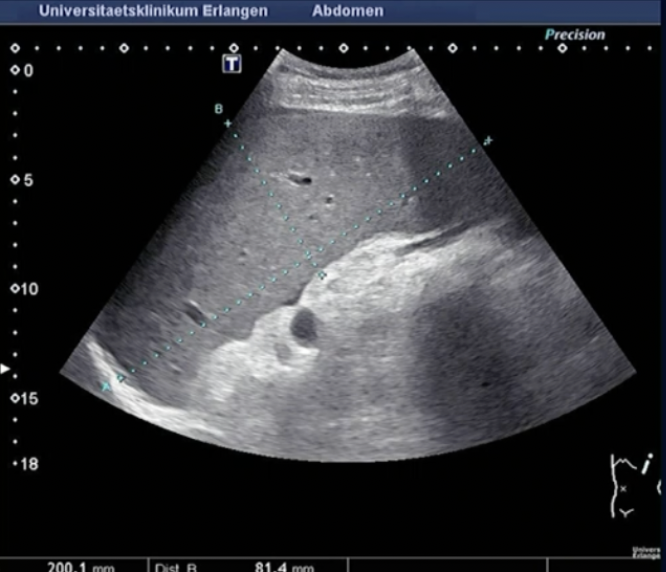

Path?

Tumour on the TAIL of Pancreas